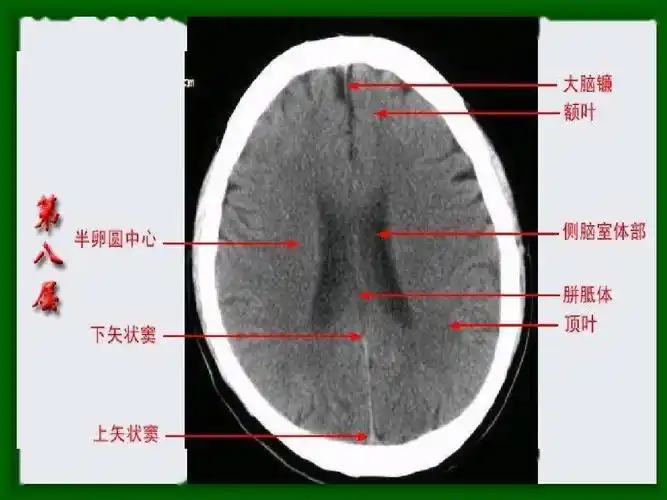

头颅ct 解剖图谱,人手一份